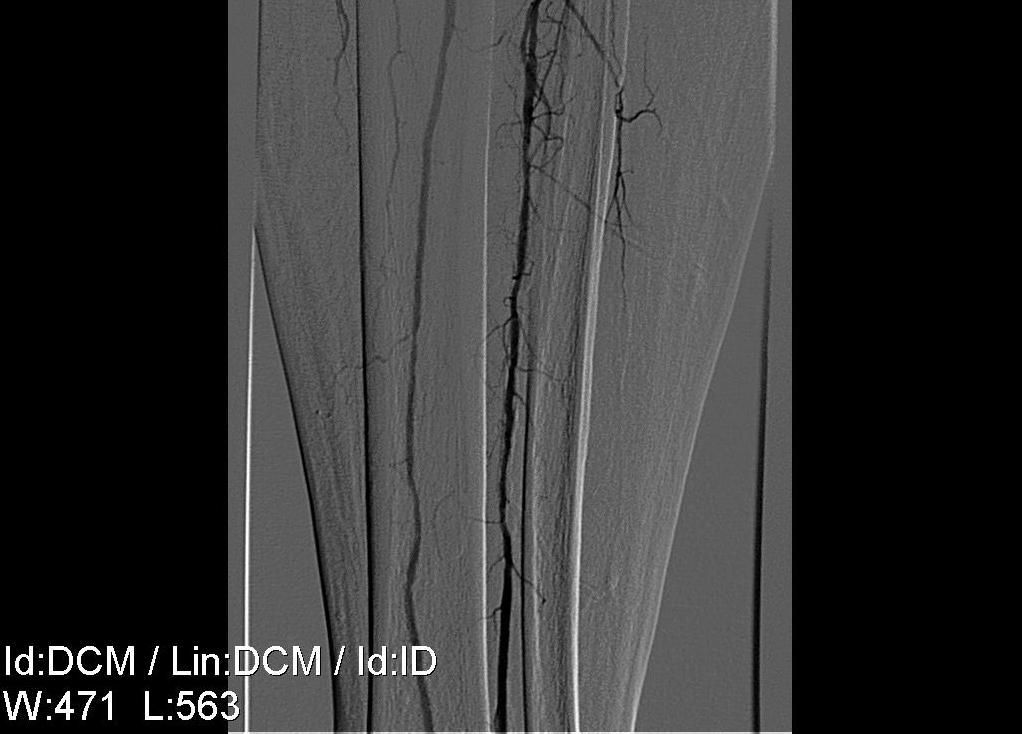

Пациент А, 1939 г.р. (68 лет).

- Атеросклероз.

- Стенозы бедренных артерий с обеих сторон.

- Окклюзия артерий обеих голеней.

- Ишемия правой нижней конечности 4 степени.

- Некроз правой стопы.

- Диабетическая полинейроангиопатия.